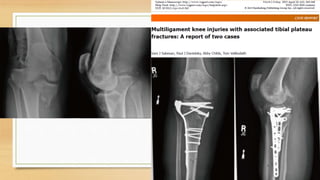

3-Lesiones multiligamentarias

asociadas a fracturas de tibia o

fémur

Las fracturas de la meseta tibial

medial se asocian con desgarros

del PLC. Las fracturas de la

meseta tibial lateral se asocian con

desgarros de MCL

Antecedentes:

Lesiones de rodilla multiligament (MKIs) con asociación a fracturas son raras pero

graves . Estas complejas lesiones de rodilla suelen ocurrir durante la participación en

Deportes de contacto o un accidente automovilístico de alta energía.

Este estudio revisa el tratamiento y los resultados para dos personas de mediana edad

(≥ cincuenta años) con fracturas de la meseta tibial y multiligamentaria de rodilla

Paciente 1:

Paciente de 52 años con fx de meseta tibial y lesión completa de LCA, LCP y LCM,

tratado con fijador externo

2.5 semanas después: RAFI con placa lateral y medial, reparación de menisco externo

2.5 a 8 semanas paciente permanece inmovilizado con brace

8 semanas: empieza la fisioterapia

16 meses: deambula, valgo de 15 grados, laxitud + 3 de LCM, Lachman +1

PACIENTE 2

Varon 59 años, fx de platillo tibial, avulsión de espina tibial anterior

Demostracion via artroscopia de lesión de LCA y LCM

1. Permanece con Brace por 8 semanas!!

2. 8 semanas RAFI de fx de platillo tibial

3. 12 semanas hay inestabilidad al estrés en valgo a 0 y 30 grados y paciente

continua con brace, se opta por tratamiento conservador para LCM

4. 1,5 años después paciente no presenta dolor ni mala alineación de rodilla